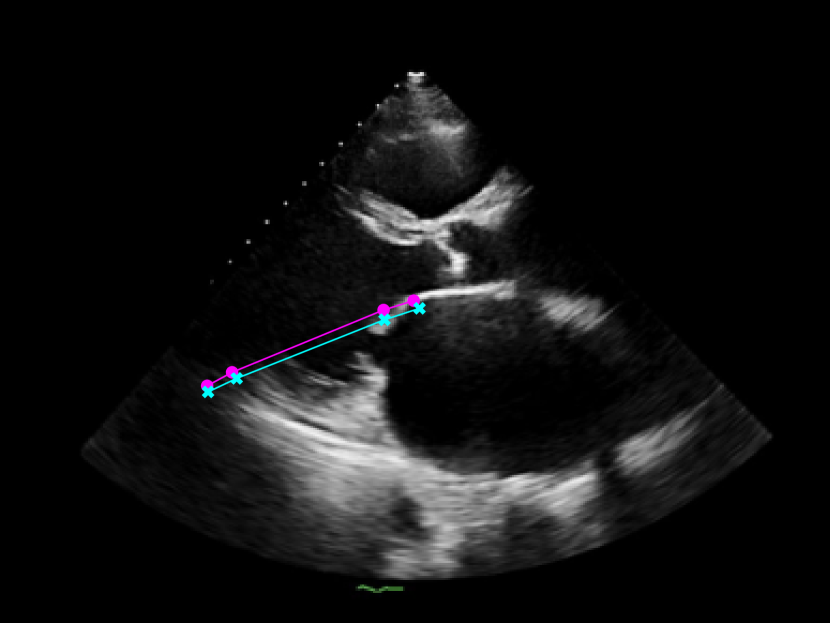

The 112x112 input is first resized to 299x299 as required by the Xception model. The Beat Extractor is then used to feed only whole beats to the LVEF estimation pipeline. A modified DeepLabV3+ model segments the left ventricle for every frame of the echocardiogram video (Figure LABEL:fig:segmentation). The area is measured, and a peak detector is then used to find the maximum (diastole) and minimum area (systole). The frame numbers corresponding to these extrema are recorded, and the video is clipped into smaller videos that go from diastole to systole. These smaller videos are independently fed to the Xception based feature extractor.

As seen in Figure 4, the model was trained to identify four key points in the echocardiogram videos: the beginning and end of the intraventricular septum (IVS), and the beginning and end of the left ventricular posterior wall (LVPW). These points were used to calculate the lengths of the IVS and LVPW, and the internal diameter of the left ventricle (LVID).